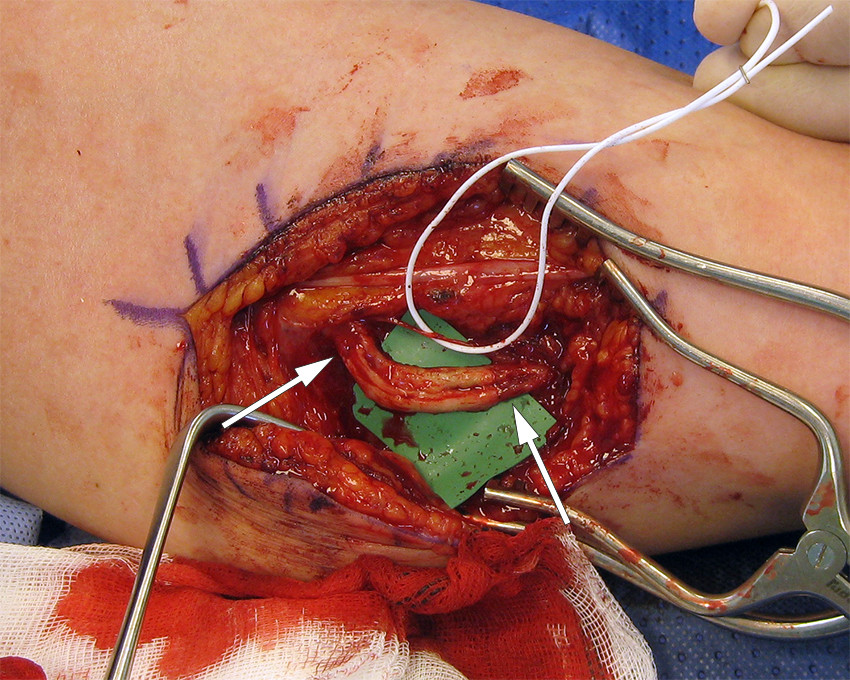

Pasient 1 ble henvist til håndkirurg på grunn av et ulnarisnerveutfall etter fjerning av p-stav. Ifølge henvisningen var implantatet ikke mulig å palpere og ble fjernet i narkose med hjelp av gjennomlysning. Pasienten fortalte at hun våknet med store smerter i overarmen med utstråling til ulnarsiden av hånden. Før henvisning var det rekvirert og utført nevrofysiologisk undersøkelse. Denne og klinisk undersøkelse tydet på et totalt ulnarisutfall med skadenivå midt på overarmen. Der forelå et 2 cm langt arr over sulcus mellom biceps og triceps, hvor lokal perkusjon utløste sterke, utstrålende smerter. Ved operasjon 2,5 måneder etter fjerningen fant vi et nevrom i kontinuitet. Et nevrom er en knute bestående av uorganisert arrvev og nervetråder. Det kan enten forekomme som et endenevrom (ved komplett overskjæring av nerven), eller som en lesjon i kontinuitet, der man vanligvis finner en arrete knute i forløpet til en tilsynelatende intakt nerve. I dette tilfellet var kun en ulnarisfasikkel intakt. Nevromet ble resesert. Defekten på 2,5 cm måtte rekonstrueres med nervegraft (nervus suralis) høstet fra venstre ben (figur 1). To år senere hadde hun stadig uttalte smerteplager og en meget dårlig hånd både sensorisk og motorisk. Hun hadde falt ut av arbeidslivet.